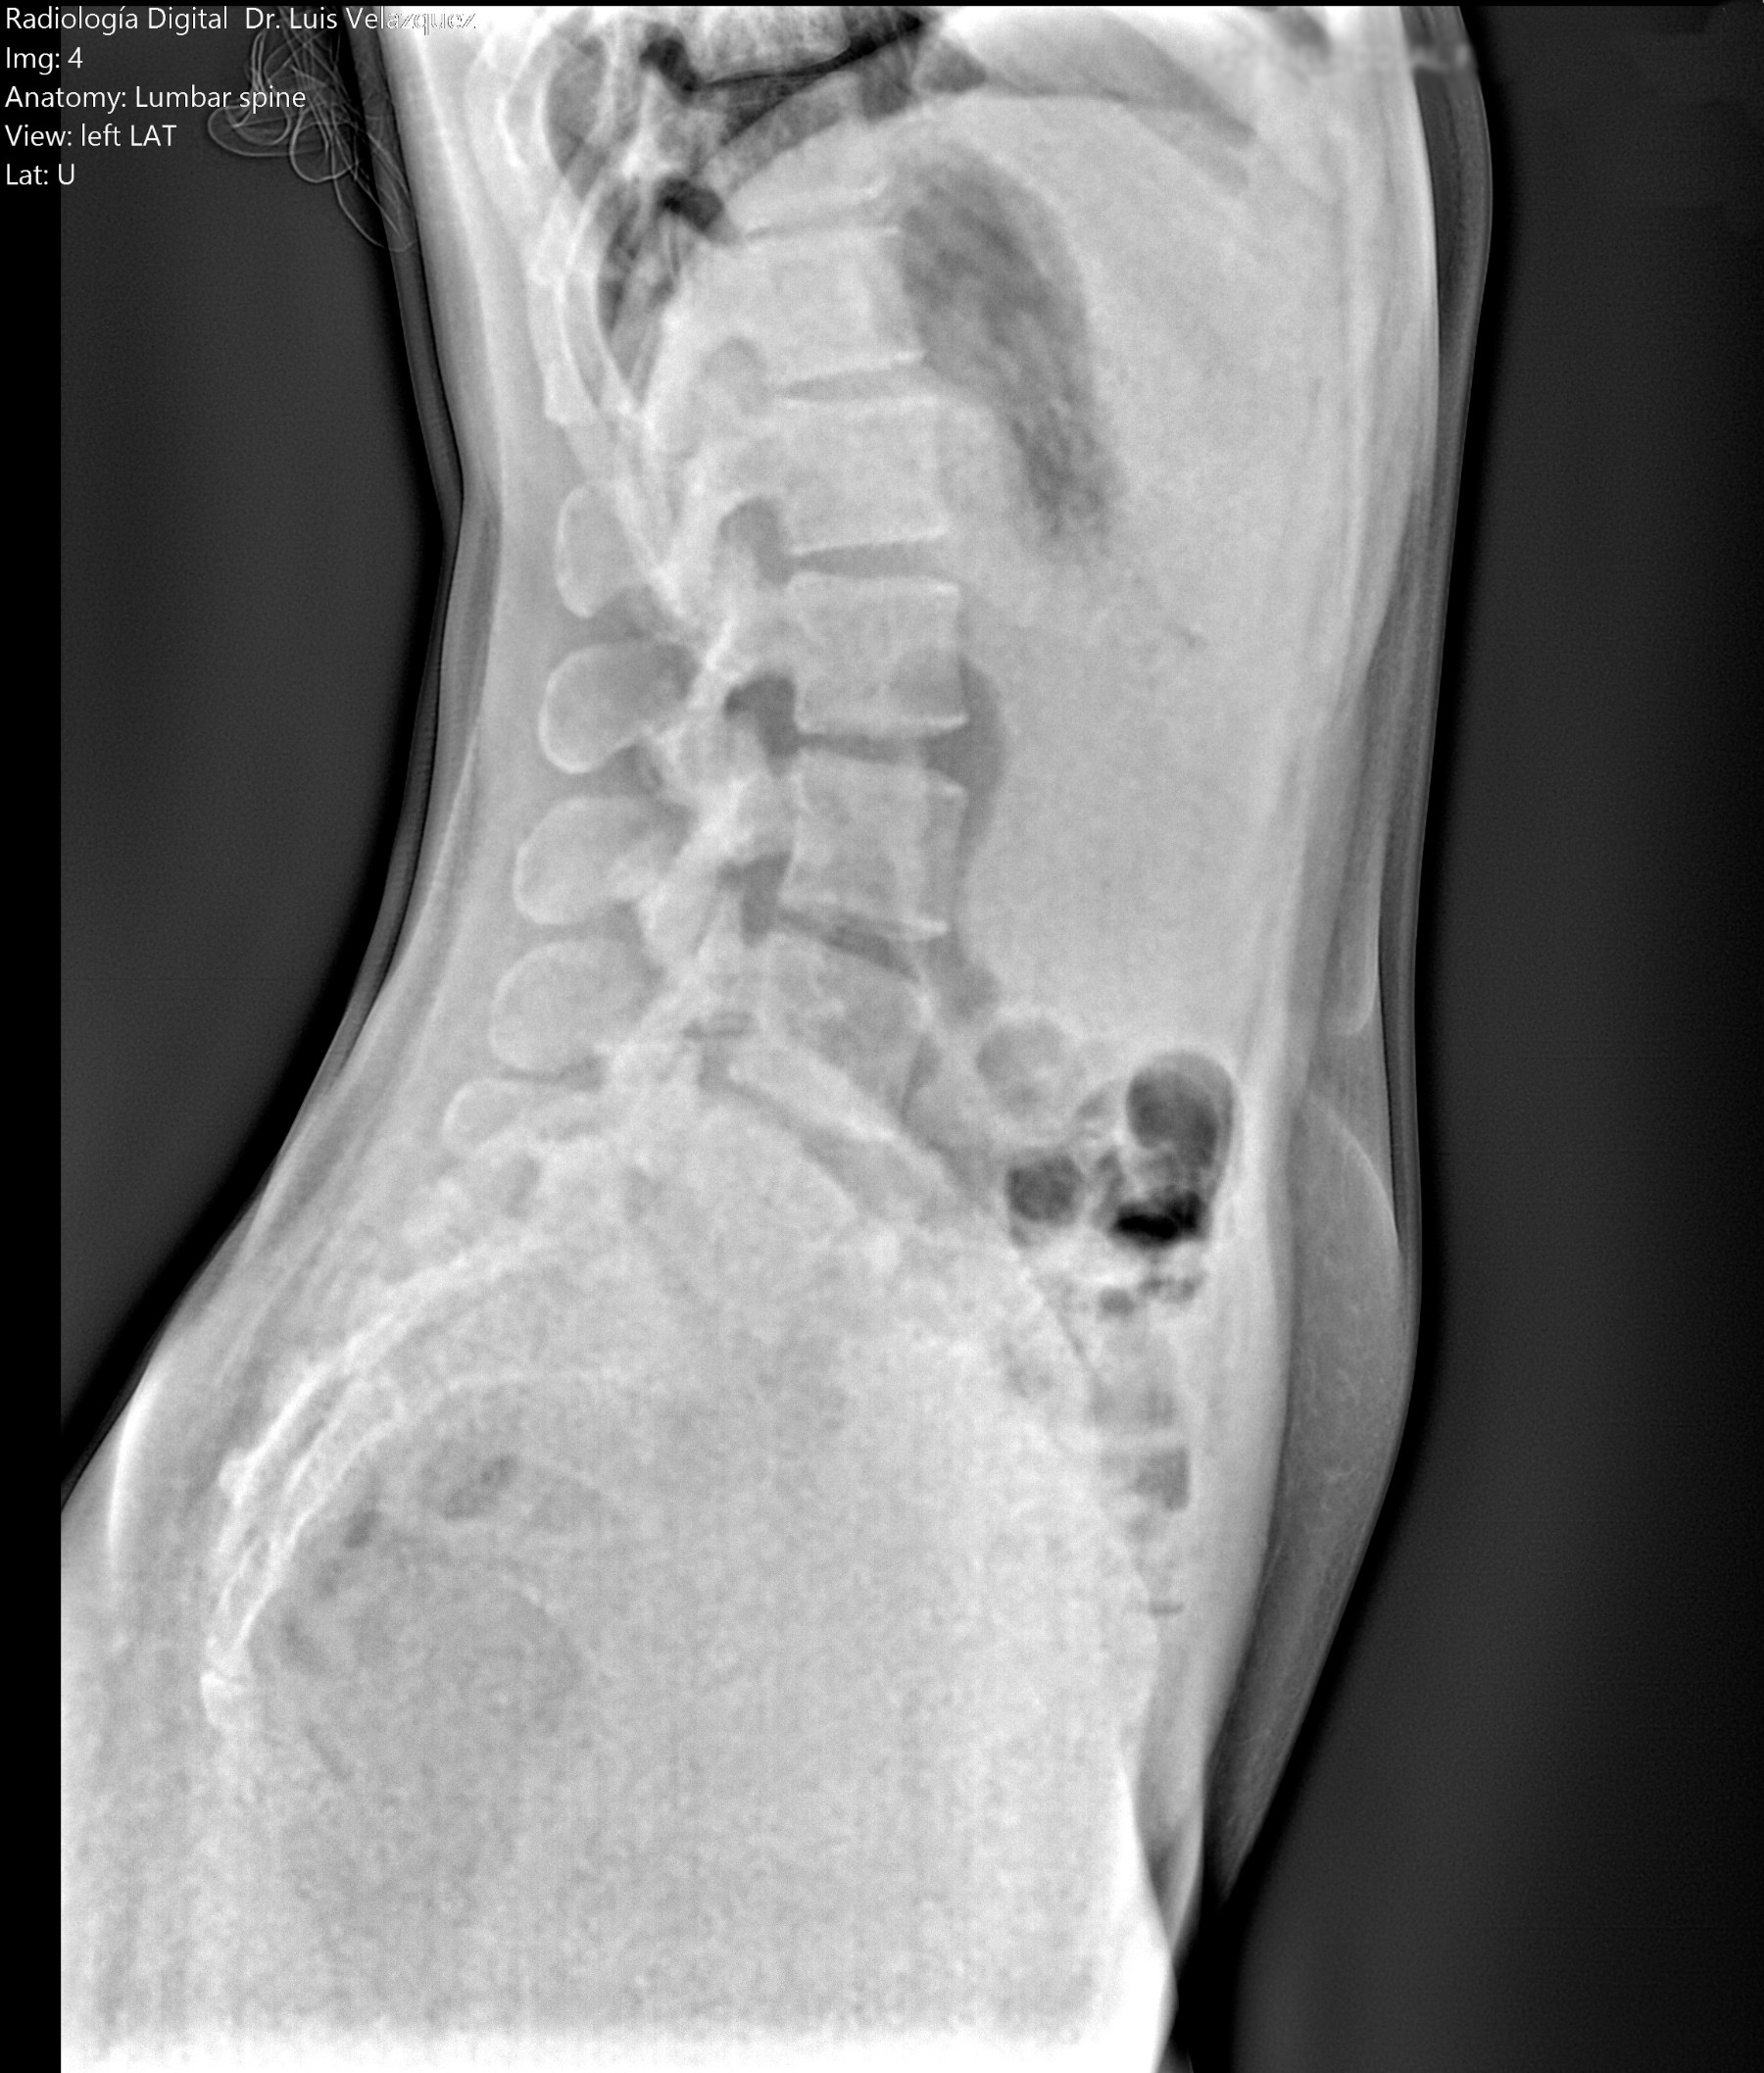

Radiología Digital como Herramienta Complementaria en el Dictamen de Bienes Muebles

Desde el descubrimiento de los rayos “X” y las placas radiográficas por Wilhelm Conrad Roentgen y su posterior difusión a través de la Asociación Físico médica de Wurzburg el 28 de diciembre de 1895, que fue la primera asociación que habló de los nuevos rayos que podían penetrar el cuerpo y fotografiar los huesos, ha habido muchos cambios tanto en la forma de obtener, procesar e incluso en la forma de visualizar, manejar y almacenar las placas radiográficas.